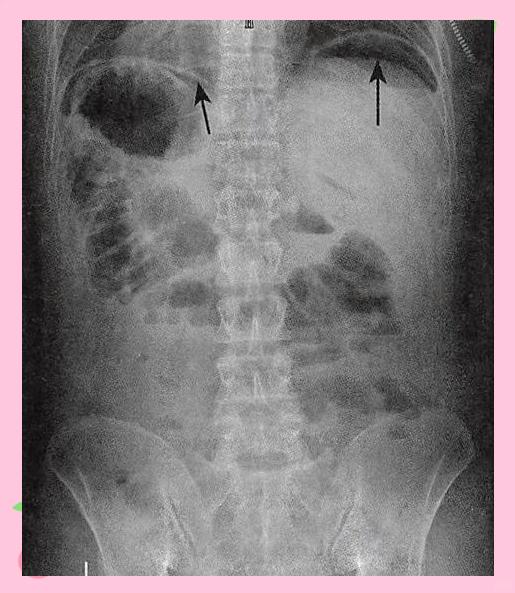

腹部平片X线诊断的常见疾病主要包括以下几类1 消化道穿孔腹部平片X线可通过观察膈下游离气体即“气腹征”诊断消化道穿孔当胃肠道破裂时,气体进入腹腔并积聚于膈下,形成特征性的新月形透亮影此征象对空腔脏器穿孔如胃十二指肠溃疡穿孔具有较高特异性,是急诊诊断的关键依据2 肠。